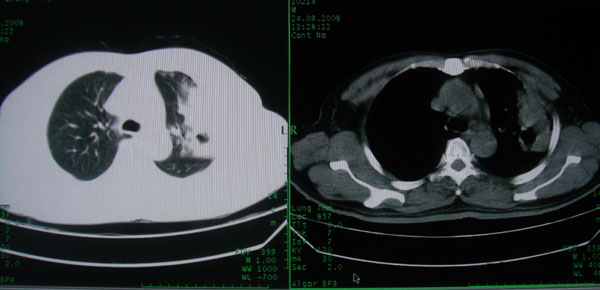

患者男性58岁因二周前起咳嗽,今天胸片示左上肺占位性病变行ct检查,无发热,无咯血痰.

左上肺感染性病变,结核伴空洞形成可能,左上肺膨胀不全

左肺上叶病灶,实变但见含气支气管、空洞但未见壁内结节及积液;

考虑:①感染性病变(包括特殊感染型肺tb)

②肿瘤性病变(考虑患者年龄比较大的关系/所以不排除)

初学者。。。左肺空洞性病变,并可见阻塞性肺不张改变,鉴于患者为老年男性,且临床症状仅有咳嗽,全身中毒症状不明显,所以我首先考虑为左肺癌性空洞并左侧肺门淋巴结转移伴左肺阻塞性肺不张。结核性空洞放于第二位考虑,可以进行相关实验室检查。希望能有病理结果,谢谢!!!!!

左肺上叶实变影,内见支气管充气征及空洞影,病人年龄较大,无发热及结核中毒症状,心影左移,未见纵隔淋巴结肿大;不知实验室检查结果如何?有否嗜酸细胞增多,有没有进行治疗?就目前资料首先考虑1.感染性病变,2.慢性嗜酸性肺炎?可结合实验室检查并短期治疗复查,肺癌不能排除。